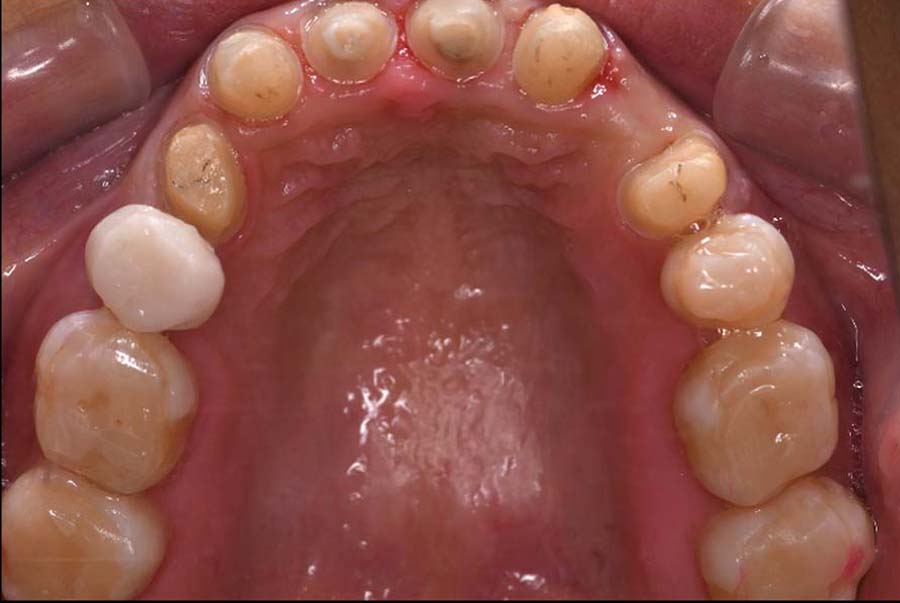

| 治療内容 | ①スプリントを装着 ②副子を装着 ③2024年4月 口腔内反映開始 ④副子を入れた状態の所まで咬合を挙上 (バイトアップ) ⑤2024年5月 上顎前歯部8本へ仮歯(TEK) を装着 |

バイトアップ後